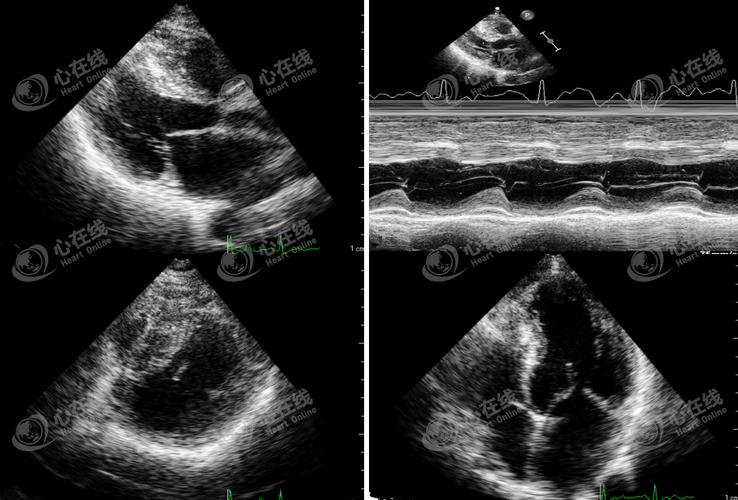

sam征超声表现,sam征

超声心动图 sam征小知识

二尖瓣可见偏心性返流,提示该患者存在sam征

实际上这幅超声图像采集自一例安装有左心室辅助装置的心衰终末期患者

sam征

sam征超声示意图

sam征超声心动图

sam现象超声图片

sam征阳性超声图片